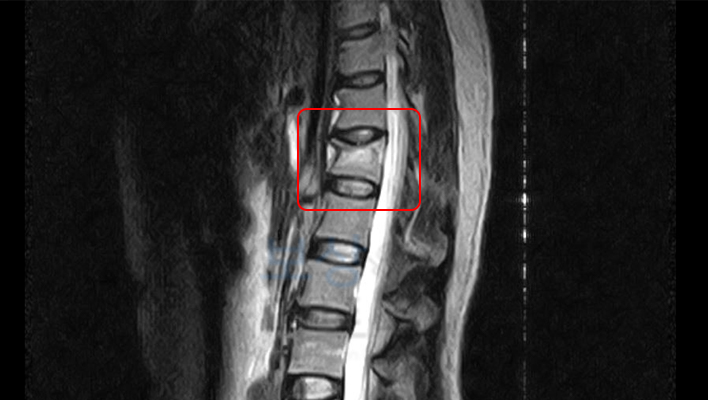

진단명 : T12 부위의 골절(S2207)

병원 겸사 결과는 "흉추 12번 골절" 이었는데요. 척추체의 골절은 보통 **「압박골절」**이라고 표현합니다. 마치 압력을 받아 찌그러지듯 골절되기 때문인데요. 다행히 골절 증상이 심하지 않아서 시술이나 수술은 하지 않았고 **TLSO 허리보조기 **만 착용하여 보존적 치료받으셨습니다.

위처럼, 의뢰인 장해 평가 결과

후유장해보험 지급률 30%

진단서를 받게 되었습니다. 저희는 성공적인 보험 청구를 위해 빠짐없이 제출 서류를 준비했는데요. 역시 이후의 보험사와의 분쟁을 피할 수는 없었습니다. 보험사에서는 현장조사와 자체 의료자문, 자료 검토를 통해 감액 의견을 보냈는데요.